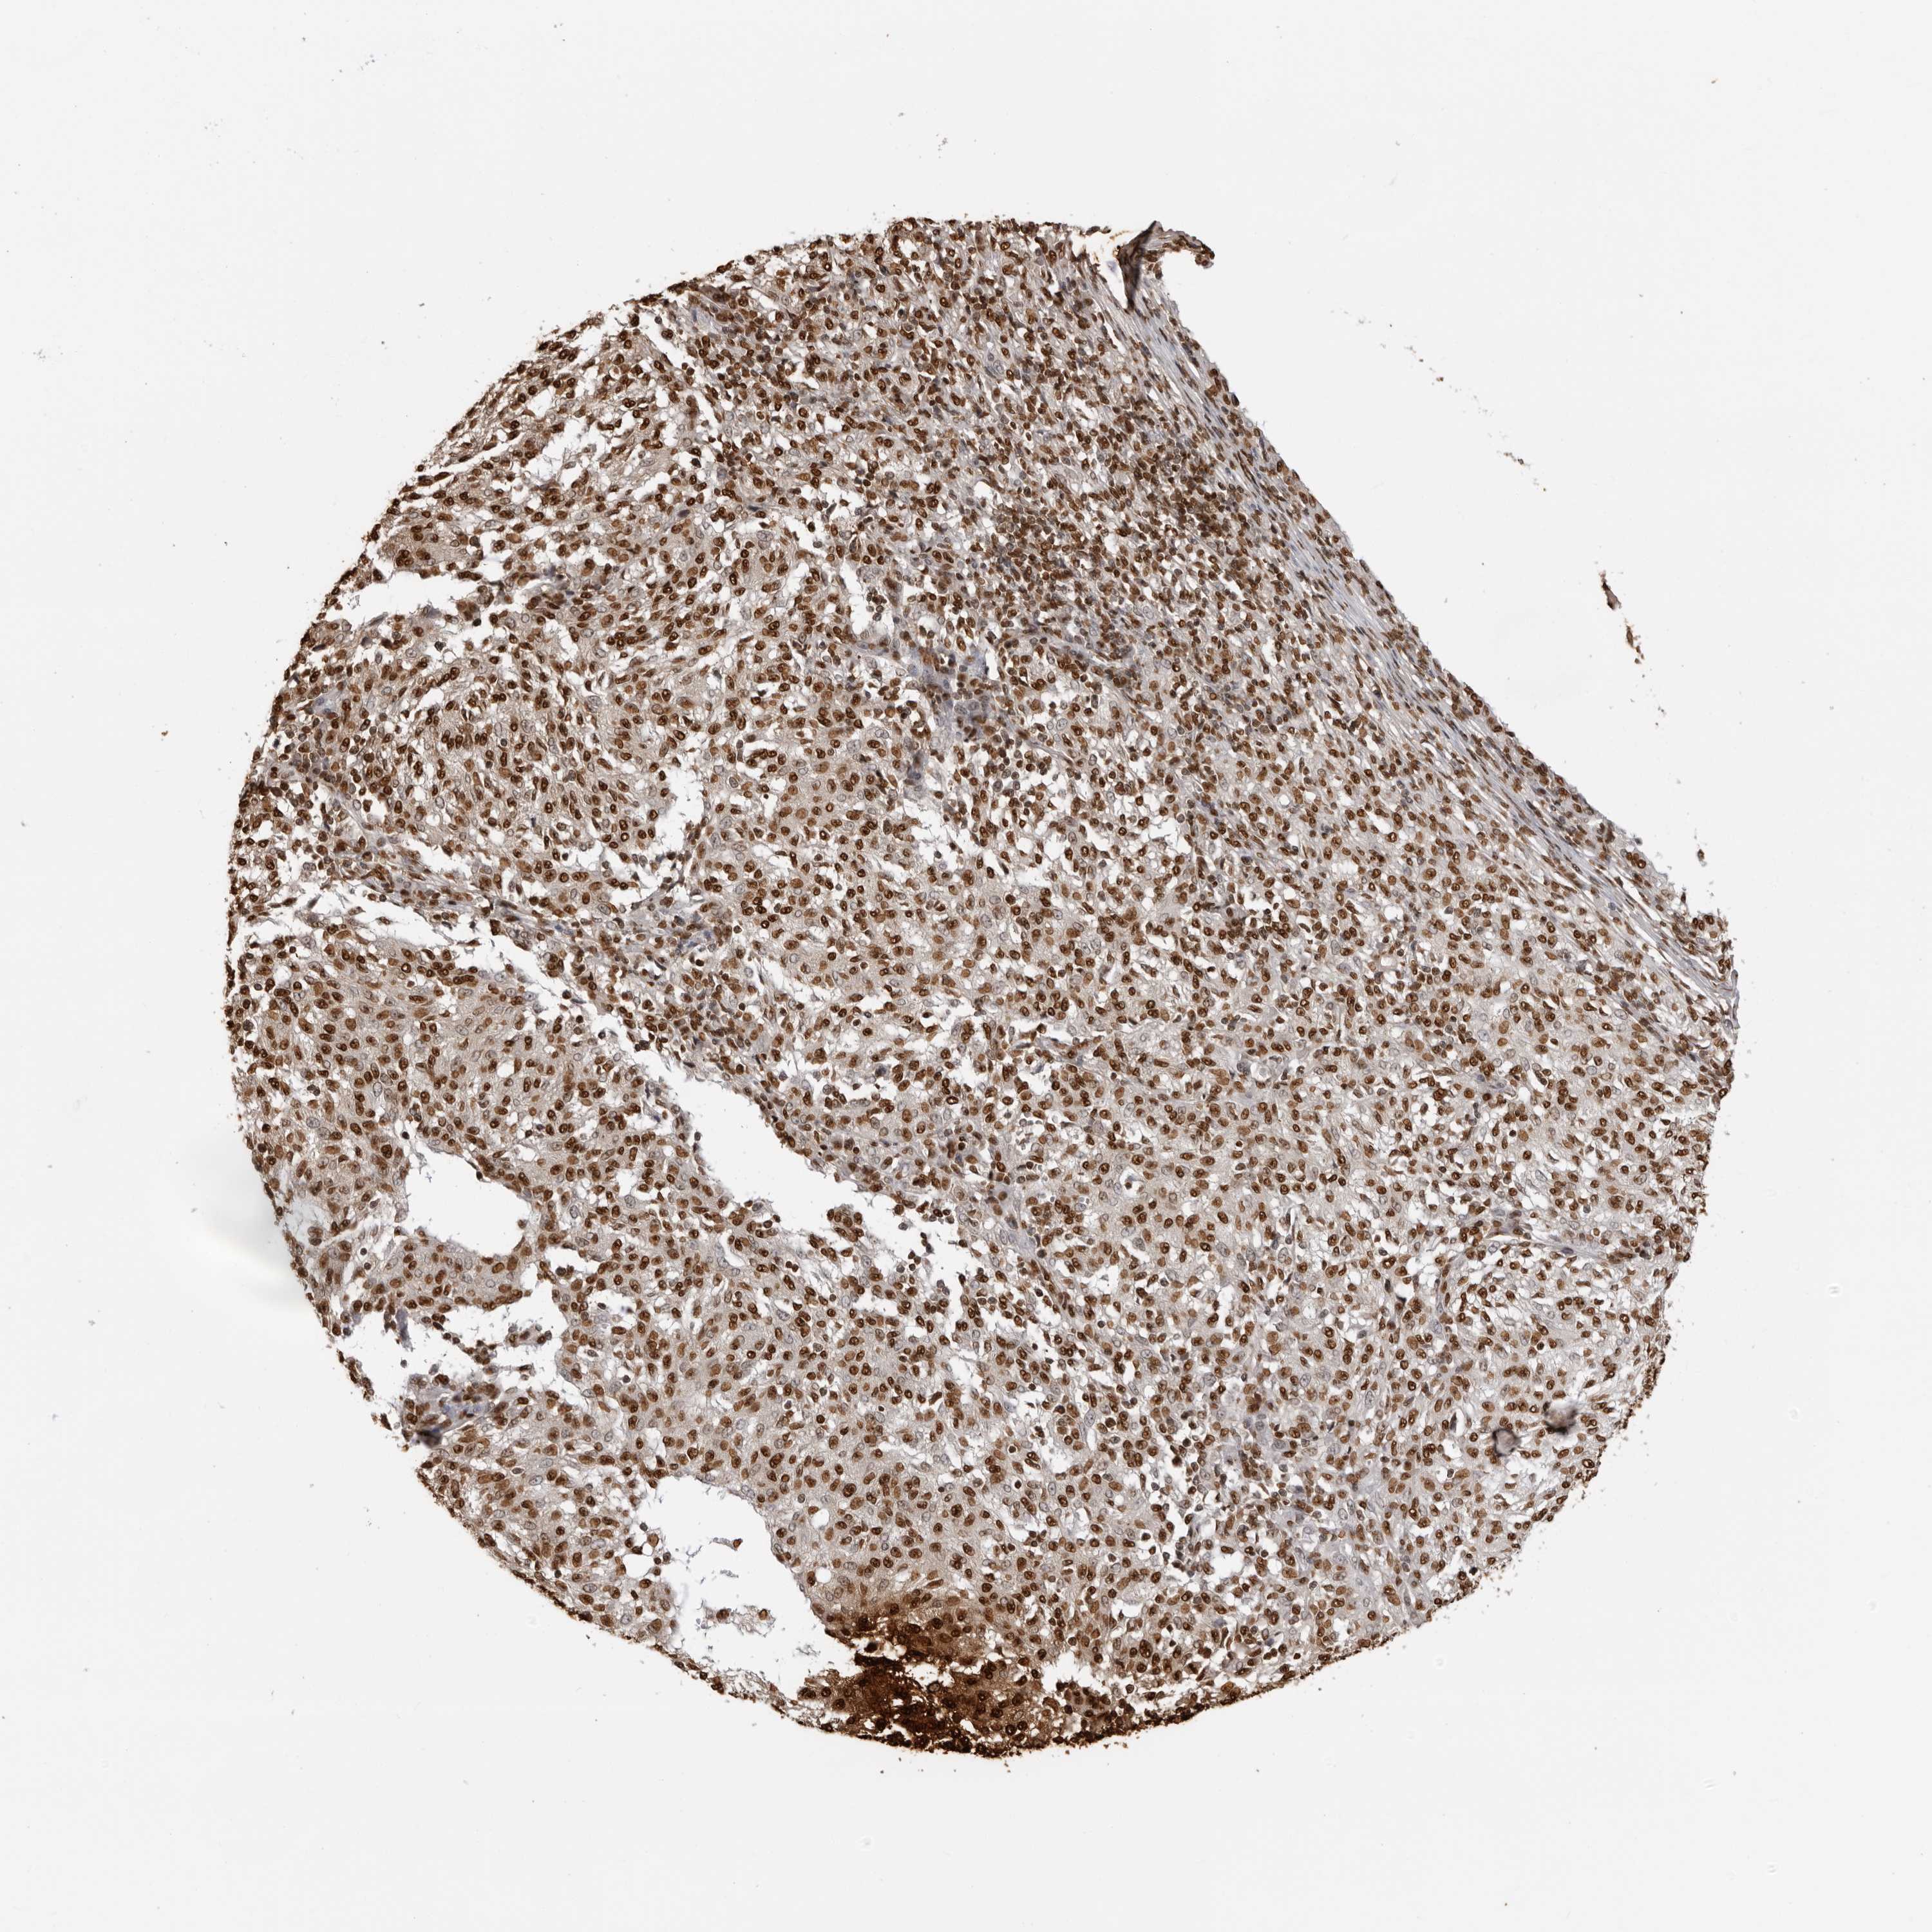

MELANOMA - Protein expressioni

A mouse-over function shows sample information and annotation data. Click on an image to view it in a full screen mode. Samples can be filtered based on level of antibody staining by selecting one or several of the following categories: high, medium, low and not detected. The assay and annotation is described here.

Note that samples used for immunohistochemistry by the Human Protein Atlas do not correspond to samples in the TCGA dataset.

Antibody stainingi

Antibody staining in the annotated cell types in the current human tissue is reported as not detected, low, medium, or high, based on conventional immunohistochemistry profiling in selected tissues. This score is based on the combination of the staining intensity and fraction of stained cells.

Each image is clickable and will lead to virtual microscopy that enables deeper exploration of all samples and also displays staining intensity scores, fraction scores and subcellular localization as well as patient and tissue information for each sample.

Antibody HPA024037

Antibody HPA065325

Antibody HPA074591

Antibody CAB025417

Staining

High

Medium

Low

Not detected

Intensity

Strong

Moderate

Weak

Negative

Quantity

>75%

75%-25%

<25%

None

Location

Nuclear

Cytoplasmic/membranous

Cytoplasmic/membranous,nuclear

Malignant melanoma, NOS

Malignant melanoma, Metastatic site